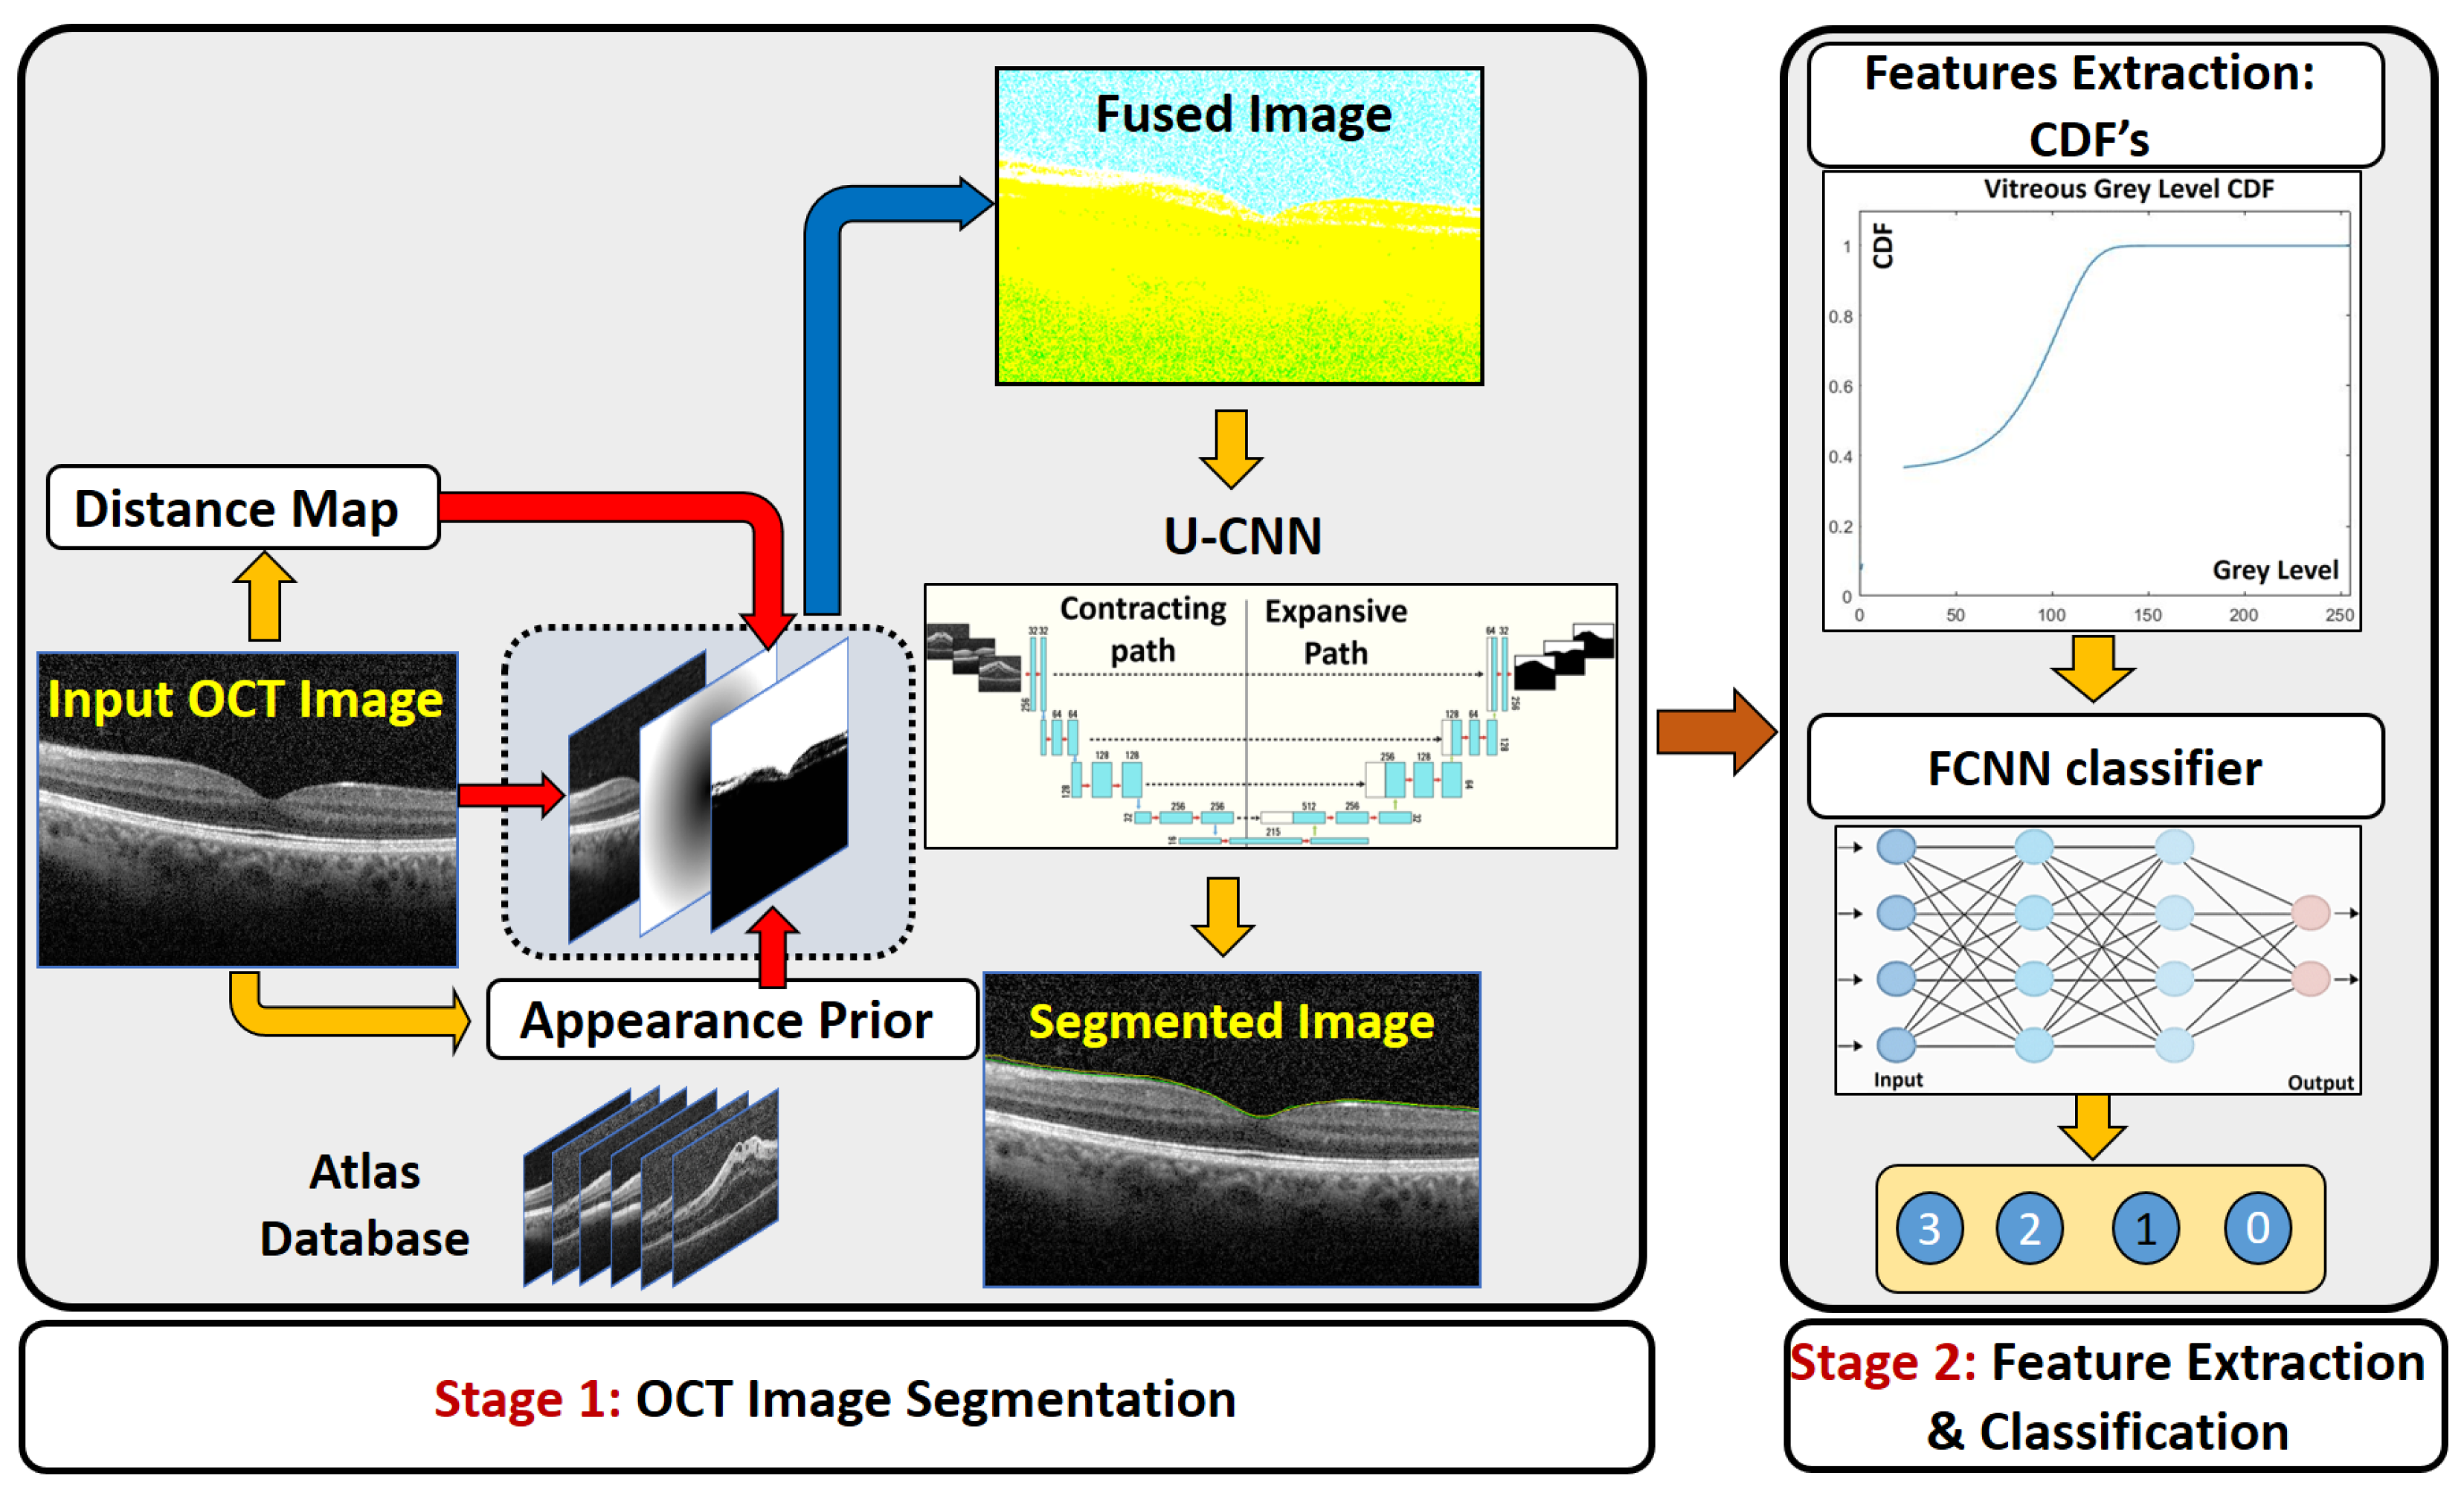

- In contrast to [16], where the OCT images were directly applied to train the U-CNN, the first stage of the proposed CAD system trains the U-CNN model using a fused image (FI) dataset, which integrates the information of the original image with a proposed distance map, and a proposed adaptive appearance map (AAP), instead of the direct original images.

- Compared to previous work, the first stage of the proposed CAD system shows superior performance in vitreous segmentation from the OCT images in spite of the great similarity between the vitreous and the background.

- The second stage of the proposed CAD system shows great performance in classification accuracy in spite of the great overlap among the extracted features from the OCT vitreous images.

2.1. Segmentation Stage

2.1.1. Construction of the Fused Image

2.1.2. U-Net Segmentation

2.2. Grading Stage